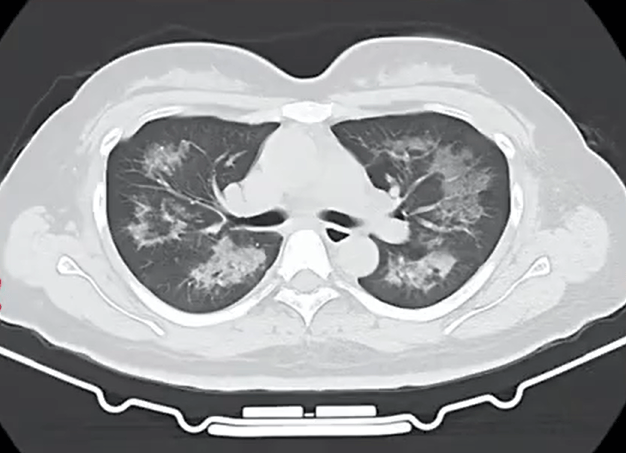

胸部CT进一步显示,她的双肺出现多发斑片状模糊影,被诊断为间质性肺炎相关资讯。医生判断,病因很可能与她近期长期接触的某类物质相关。经过医生反复细致地询问病史,小江才说出自己存在长期、频繁使用定妆喷雾的情况。